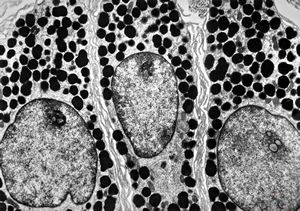

F, 24y. | molluscum contagiosum … virions

F, 24y. | molluscum contagiosum